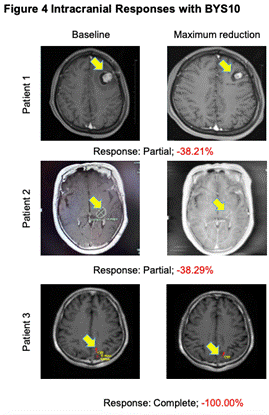

高效入脑:BYS10治疗伴脑转移RET突变实体瘤实现颅内缓解

研究职员在4例至少有1个可丈量颅内病灶(1例颅内完全缓解)的患者中视察到颅内抗肿瘤活性。。。。。

图4.颅内抗肿瘤活性

从本次ASCO大会所宣布的高选择性RET抑制剂BYS10宣布了首项Ⅰ/Ⅱ期人体研究效果来看,,,,,,BYS10在RET实体瘤治疗领域具有很是大的潜力:首先,,,,,,清静性效果充分批注,,,,,,BYS10治疗RET突变实体瘤的清静性优异,,,,,,3-4级TRAE及严重不良反应的爆发率低,,,,,,利于患者恒久治理。。。。。其次,,,,,,起源疗效数据效果显示,,,,,,患者治疗后的ORR为62.5%,,,,,,DCR为85%,,,,,,这批注近三分之二的患者经由BYS10治疗能够有用实现疾病缓解,,,,,,凌驾五分之四的患者能够实现疾病控制,,,,,,尤其TC和MTC患者的DCR可抵达100%。。。。。在临床上更为常见的NSCLC患者中,,,,,,BYS10治疗的ORR能够抵达60%,,,,,,DCR能够抵达80%,,,,,,充分展现了BYS10的治疗潜能。。。。。别的,,,,,,关于临床上十分关注的脑转移患者,,,,,,经BYS10治疗后可实现颅内病灶的有用缓解,,,,,,证实了BYS10的颅内病灶控制潜能。。。。。